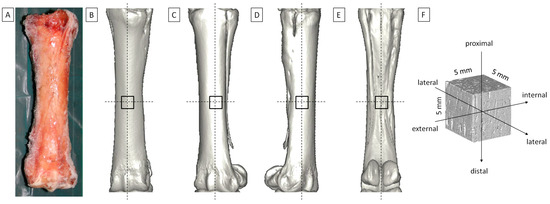

2.1. Biological Samples

2.2. CT Imaging